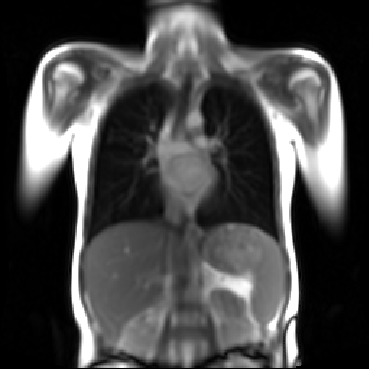

Refer to captionRefer to captionRefer to captionRefer to captionRefer to captionRefer to captionRefer to captionRefer to captionRefer to captionRefer to captionRefer to captionRefer to captionRefer to captionRefer to caption

Figure 5: Maximum inspiration (top row) and maximum expiration (bottom row) for different slice positions of one patient from back to front.

For a complete chest volume coverage, the lung is scanned at different slice positions as shown in Figure 5. At each slice position, a dynamic 2D+t image series with 140 images is acquired. For the further analysis of the image data, all images of one slice position need to be spatially aligned. We choose the image which is closest to the mean respiratory cycle as fixed image of the series. The other images of the series are then registered to this image. Our data set consists of 48 lung acquisitions of 42 different patients. Each lung scan contains between 7 and 14 slices. We used the data of 34 patients for the training set, 4 for the evaluation set, and 4 for the test set.